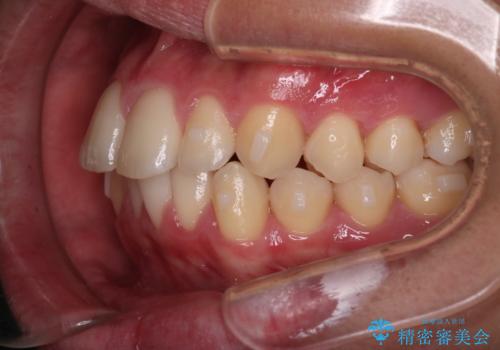

【インビザラインモニター】前歯が出ているのが気になる

- 上の前歯が出ているのが少し気になるとの事で来院されました。

インビザライン希望のため、IPR(歯と歯の間を削る処置)を行うことで、前歯の位置とがたつき整える治療計画を立てました。

患者様よりシュミレーション通りに歯が動くか心配との事だったので

出来るだけ計画通りに歯を動かすために、マウスピース1枚あたりの使用時間を長めに使っていただきました。

そのため、多少治療期間が延びましたが、リファイメント(マウスピースの再発注)なしで終了することができました。